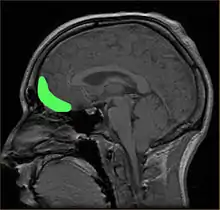

إن مجموعة كبيرة من الأبحاث تشير أن الاعتلال النفسي مرتبط مع ردود فعل غير نموذجية لمنبهات الشدة (مثل تعابير الوجه والتعابير الصوتية للخوف والحزن )، بما في ذلك نقص تفعيل المناطق القشرية مغزلية الشكل والمناطق القشرية خارج الجسم المخطط التي قد تكون مسؤولة جزئيا عن الخلل في المعرفة وانخفاض الاستجابة اللاإرادية لتعابير مع ضعف التعاطف.[34] إن الأوجه الحيوية الأساسية لمعالجة تعابير السعادة تكون سليمة وظيفيًا لدى المصابين بالاعتلال النفسي على الرغم من أنها أقل استجابة من تلك الموجودة في مجموعة الضبط. إن أدبيات التصوير العصبي غير واضحة في تحديد فيما إذا كانت أوجه القصور خاصة بمشاعر معينة مثل الخوف. يشير النمط العام للنتائج عبر الدراسات إلى أن الأشخاص الذين تم تشخيص إصابتهم باعتلال نفسي يظهرون انخفاضًا في نشاط التصوير بالرنين المغناطيسي والرنين المغناطيسي الوظيفي والرنين المغناطيسي المضخم وفحص التصوير المقطعي بالإصدار البوزيتروني و التصوير المقطعي المحوسب بانبعاث الفوتون الواحد في مناطق الدماغ.[77] أظهرت الأبحاث أيضًا أن حجم اللوزة الدماغية (بالإنجليزية: amygdala) التي بدت أصغر بنسبة 18٪ تساهم في انخفاض الإحساس العاطفي بشكل ملحوظ فيما يتعلق بالخوف والحزن، من بين المشاعر السلبية الأخرى، وهذا الأمر قد يكون سببًا يفسر كون الأفراد المصابين بالاعتلال النفسي لديهم تعاطف أقل.[78] أفادت بعض دراسات الرنين المغناطيسي الوظيفي الحديثة أن عيوب الإدراك العاطفي في الاعتلال النفسي منتشرة عبر المشاعر (الإيجابية والسلبية).[79][80][81][82][83] كما أظهرت الدراسات التي أجريت على الأطفال ذوي الميول للاعتلال النفسي مثل هذه الارتباطات.[83][84][85][86][87][88] وجدت التحليلات التلوية أيضًا دليلًا على ضعف في التعرف على المشاعر الصوتية والوجهية للعديد من المشاعر (أي ليس فقط الخوف والحزن) لدى كل من البالغين والأطفال / المراهقين.[89]

تم اقتراح المناطق الجبهية واللوزة باعتبارها ذات أهمية خاصة.[73] يبدو أن الأشخاص الذين حصلوا على 25 درجة أو أعلى في قائمة تدقيق هير للاعتلال النفسي مع وجود قصة مرتبطة بالسلوك العنيف قد كان لديهم تكامل قليل جدا في البنية المجهرية للمادة البيضاء التي تربط اللوزة مع القشرة الجبهية الحجاجية (مثل الحزمة غير المحددة). أشارت الأدلة إلى أن درجة الشذوذ كانت مرتبطة بشكل كبير بدرجة الاعتلال النفسي وقد تفسر السلوكيات المخالفة.[74] علاوة على ذلك ارتبطت التغيرات في اللوزة بالسمات "القاسية غير العاطفية" عند الأطفال. ومع ذلك فقد ارتبطت اللوزة أيضًا بالعواطف الإيجابية وكانت هناك نتائج غير متسقة في الدراسات في مجالات معينة والتي قد تكون بسبب مشكلات منهجية.[4]